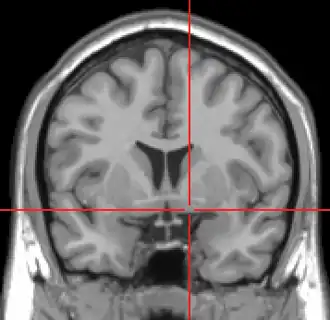

Coronal MRI slice with cross-hairs indicating location of the substantia innominata | |